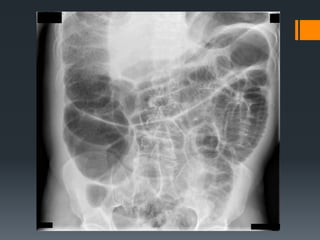

Radiologia simple:

De abdomen en decubito y en bipedestracion

Niveles hidroaereos con forma de “U”

invertida (en bipedestracion)

Si la obstrucciòn afecta al colon, la

distribucion del gas es periferica.

El signo de “grano de cafe” indica el vòlvulo

intestinal.

La presencia de aire libre es signo de

perforaciòn intestinal.